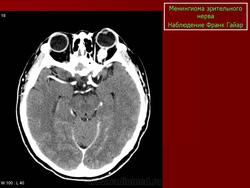

Менингиома появляется в возрасте 20—60 лет, чаще у женщин. Опухоль развивается из арахноидальных ворсинок, расположенных между твердой и паутинной оболочками. Диаметр зрительного нерва, пораженного опухолью, увеличивается в 4— 6 раз и может достигать 50 мм. Менингиома способна прорастать оболочки зрительного нерва и распространяться на мягкие ткани орбиты. Как правило, опухоль односторонняя, характеризуется экзофтальмом с ранним снижением зрения. При прорастании тканей орбиты возникает ограничение движений глаза. На глазном дне — резко выраженный застойный диск зрительного нерва, реже — его атрофия. Появление значительно расширенных вен синюшного цвета на застойном диске свидетельствует о распространении опухоли непосредственно до заднего полюса глаза.

Диагностика менингиомы трудна, так как даже на компьютерных томограммах, особенно в начальной стадии заболевания, зрительный нерв не всегда настолько увеличен, чтобы предположить его опухолевое поражение. Лечение — операция или лучевая терапия. Прогноз для зрения неблагоприятный. При росте опухоли вдоль ствола зрительного нерва имеется угроза распространения ее в полость черепа и поражения хиазмы. Прогноз для жизни благоприятный при расположении опухоли в пределах полости орбиты.